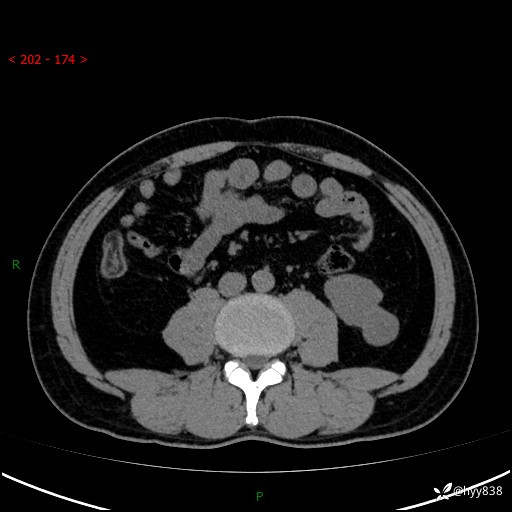

中年男性,左侧腰背部间断性胀痛不适。第一眼“乳头或囊肿”,有无意外---(有结果)

【患者信息】:41岁/男

【主诉】:左侧腰背部间断性胀痛不适1周

【现病史及既往史】:患者1周前无明显诱因出现左侧腰部疼痛,呈间断性胀痛,休息后可缓解,无放射痛,偶可见肉眼血尿,无血块,无尿频尿急尿痛,无夜尿增多,无畏寒发热、咳嗽咳痰等症状。于我院查双肾CT示:左肾占位性病变,左肾下极囊性病变,左肾轻度积水,胆囊多发结石。今为求进一步诊治来我院,门诊以“左肾占位性病变”收治入院。 起病以来,患者精神佳,饮食、睡眠良好,大便正常,小便如上诉,体力体重无明显变化。

【检查】:肾脏CT平扫+增强